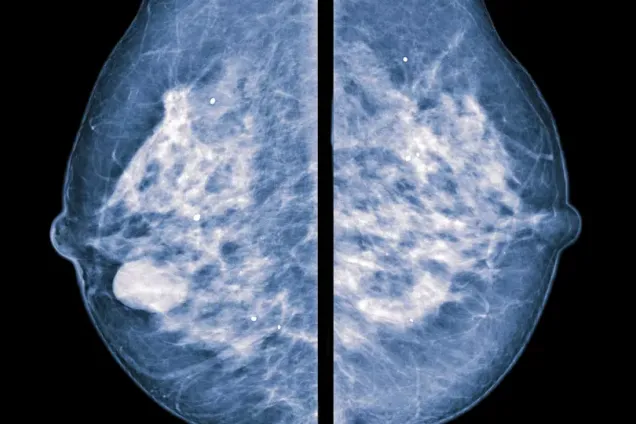

SCAN-B (Sweden Cancerome Analysis Network - Breast), is a is a large-scale research project that began in 2010 in southern Sweden, centered in Lund. The goal of the project is to analyze the genomic makeup of breast cancer tumors to improve patient outcomes through more individualized treatment.